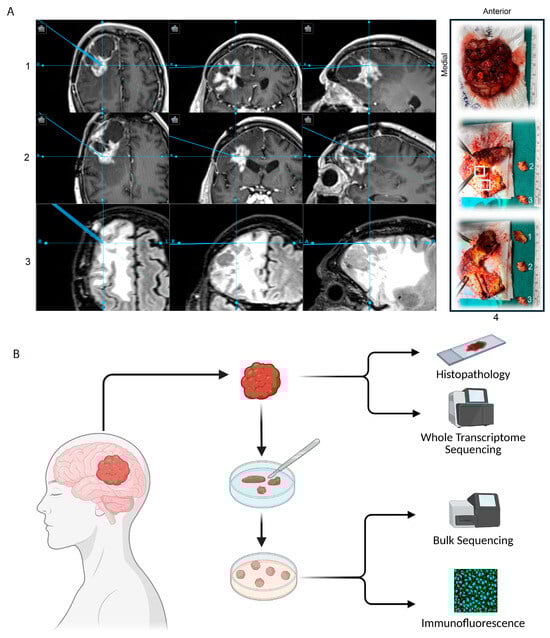

Precision Oncology for High-Grade Gliomas: A Tumor Organoid Model for Adjuvant Treatment Selection

High-grade gliomas (HGGs) are aggressive brain tumors with limited treatment options and poor survival outcomes. Variants including isocitrate dehydrogenase (IDH)-wildtype, IDH-mutant, and histone 3 lysine to methionine substitution (H3K27M)-mutant subtypes demonstrate considerable tumor heterogeneity at the genetic, cellular, and microenvironmental levels. This presents a major barrier to the development of reliable models that recapitulate tumor heterogeneity, allowing for the development of effective therapies. Glioma tumor organoids (GTOs) have emerged as a promising model, offering a balance between biological relevance and practical scalability for precision medicine. In this study, we present a refined methodology for generating three-dimensional, multiregional, patient-derived GTOs across a spectrum of glioma subtypes (including primary and recurrent tumors) while preserving the transcriptomic and phenotypic heterogeneity of their source tumors. We demonstrate the feasibility of a high-throughput drug-screening platform to nominate multi-drug regimens, finding marked variability in drug response, not only between patients and tumor types, but also across regions within the tumor. These findings underscore the critical impact of spatial heterogeneity on therapeutic sensitivity and suggest that multiregional sampling is critical for adequate glioma model development and drug discovery. Finally, regional differential drug responses suggest that multi-agent drug therapy may provide better comprehensive oncologic control and highlight the potential of multiregional GTOs as a clinically actionable tool for personalized treatment strategies in HGG. Full article

Show Figures

Graphical abstract